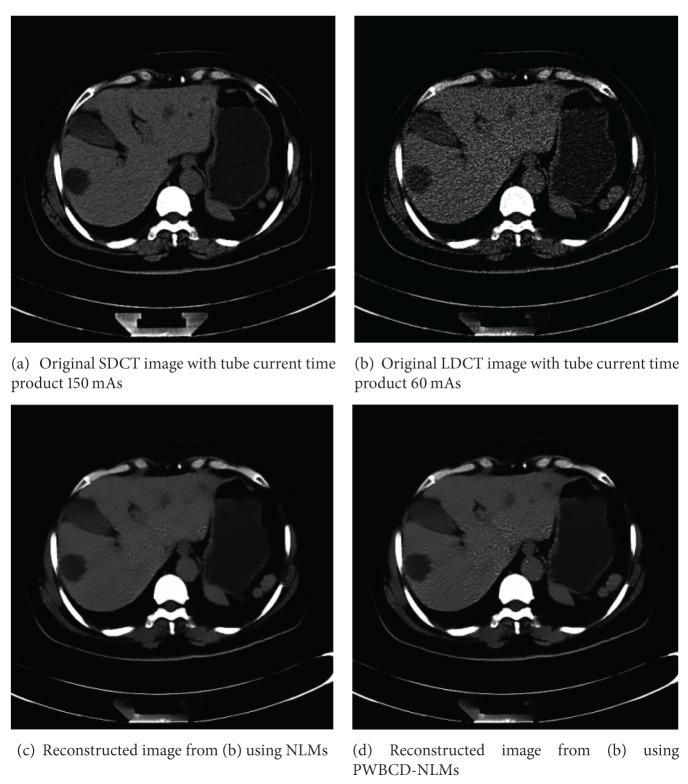

NLMs is a state-of-art image denoising method; however, it sometimes oversmoothes anatomical features in low-dose CT (LDCT) imaging. In this paper, we propose a simple way to improve the spatial adaptivity (SA) of NLMs using pointwise fractal dimension (PWFD). Unlike existing fractal image dimensions that are computed on the whole images or blocks of images, the new PWFD, named pointwise box-counting dimension (PWBCD), is computed for each image pixel. PWBCD uses a fixed size local window centered at the considered image pixel to fit the different local structures of images. Then based on PWBCD, a new method that uses PWBCD to improve SA of NLMs directly is proposed. That is, PWBCD is combined with the weight of the difference between local comparison windows for NLMs. Smoothing results for test images and real sinograms show that PWBCD-NLMs with well-chosen parameters can preserve anatomical features better while suppressing the noises efficiently. In addition, PWBCD-NLMs also has better performance both in visual quality and peak signal to noise ratio (PSNR) than NLMs in LDCT imaging.

NLMs 是一种先进的图像去噪方法;然而,它有时会过度平滑低剂量 CT(LDCT)成像中的解剖特征。在本文中,我们提出了一种使用逐点分形维数(PWFD)来提高 NLMs 空间自适应性(SA)的简单方法。与现有的在整幅图像或图像块上计算的分形图像维数不同,新的 PWFD,称为逐点盒计数维数(PWBCD),是为每个图像像素计算的。PWBCD 使用以考虑的图像像素为中心的固定大小局部窗口来拟合图像的不同局部结构。然后,基于 PWBCD,提出了一种直接使用 PWBCD 来改进 NLMs 的 SA 的新方法。也就是说,PWBCD 与 NLMs 中局部比较窗口之间差异的权重相结合。测试图像和真实正弦图的平滑结果表明,选择合适参数的 PWBCD-NLMs 可以在有效抑制噪声的同时更好地保留解剖特征。此外,PWBCD-NLMs 在 LDCT 成像中的视觉质量和峰值信噪比(PSNR)方面也优于 NLMs。